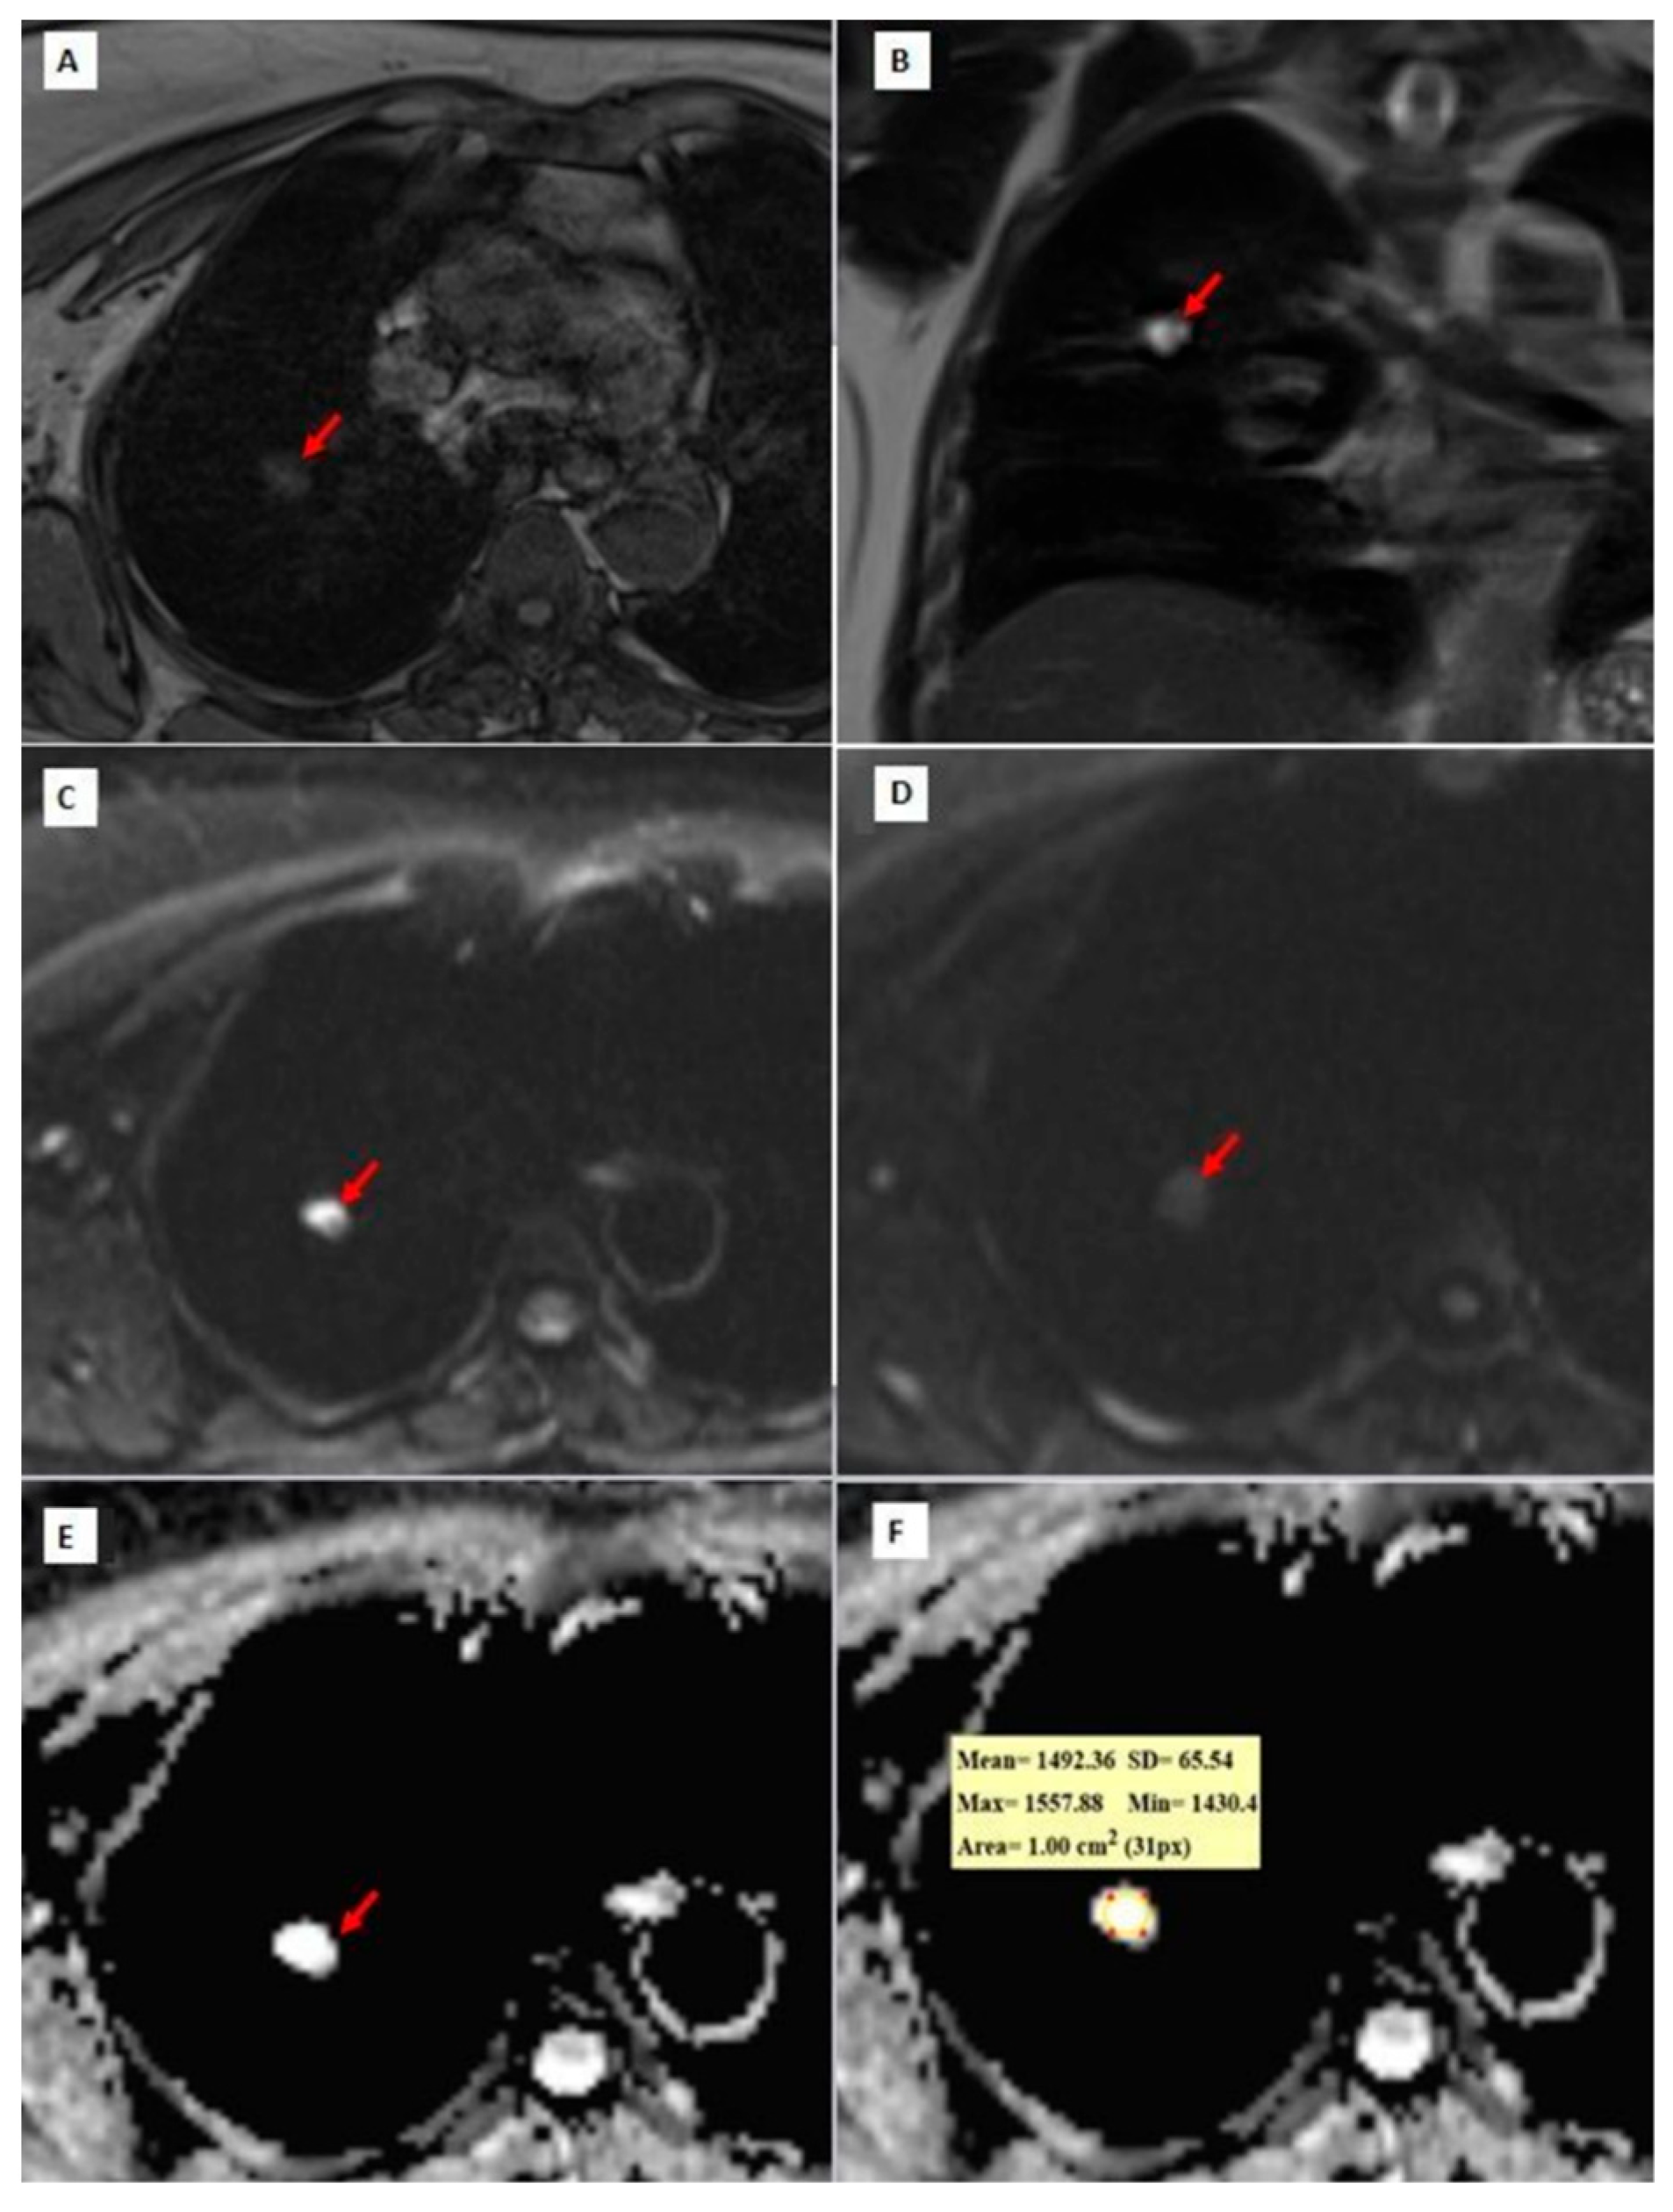

Figure 3, Figure 4 and Figure 5 show thorax MRI images of patients with tumors in the grade 1, 2, and 3 categories, respectively.

Figure 5. A 68-year-old patient with grade 3 squamous cell carcinoma. (A,B) b = 0 and b = 800 DW images, respectively. A heterogeneous left upper lobe lung mass (red arrows). (C,D). ADC maps showing a heterogeneous mass and a mean ADC value of 1107.45 × 10−6 mm2/s.